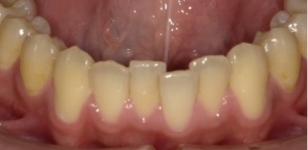

観察方法はPARスコアではなく、もう少しダイレクトな評価になるリトル教授らの方法を使いました。つまり右図のように、後戻りが一番現れやすいと言われている下の前歯において、歯と歯の接触点間の距離をmm単位でデジタル写真上で計測し、それらの合計のミリ数を「指数」とするものです。歯並びが綺麗であれば“0”に近い数字になり、数字が大きいと悪い歯並びを意味します。この写真の歯と歯の接触点間の距離の合計は9.3mmでしたから、指数は9.3になります。

永久歯を抜かずに矯正できたが、自然な歯並びの変化(犬歯部で狭くなる)のために、下顎前歯にガタツキが発生した。